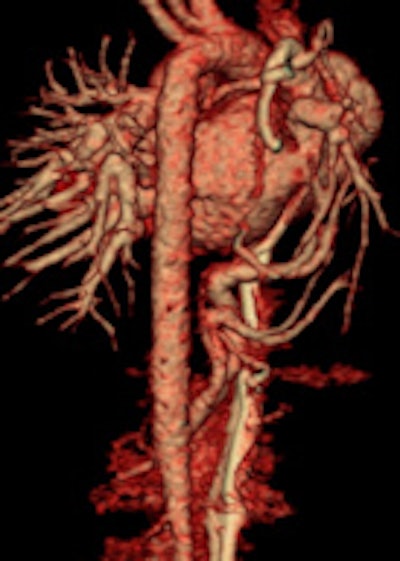

Prospective ECG-gated study on an unsedated free-breathing 2-month-old girl with an average heart rate of 122 beats per minute (bpm). The right pulmonary artery is hypoplastic (top left). An aortopulmonary collateral arising from the celiac axis supplies the right lung, as shown in the volume-rendered image (top right) and the maximum intensity projection image (bottom). All figures courtesy of Carolyn Young.